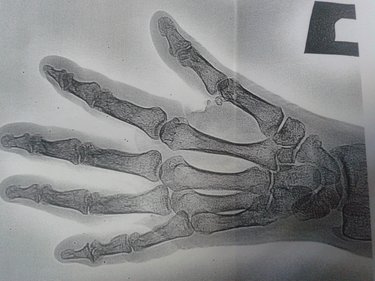

Быстро, думаю, с любовью к профессии, осмотрел мою кисть. Отправил в рентген- кабинет.

Вернулась без снимка- всё отразилось на экране компьютера Кима. «Прогресс!»- мелькнуло в голове.

В поликлинике Леонтьева Надежда Васильевна- хирург «от бога» попросила мои снимки.

Леонтьева посмотрела на снимки.

- Перелома нет!- мило произнесла Надежда Васильевна.

- Зачем замуровали руку?- хотелось добавить к вопросу обращение-«демоны».

- Непонятно,- врач развела руками и отправила в смежный процедурный кабинет, где мне сняли гипс.